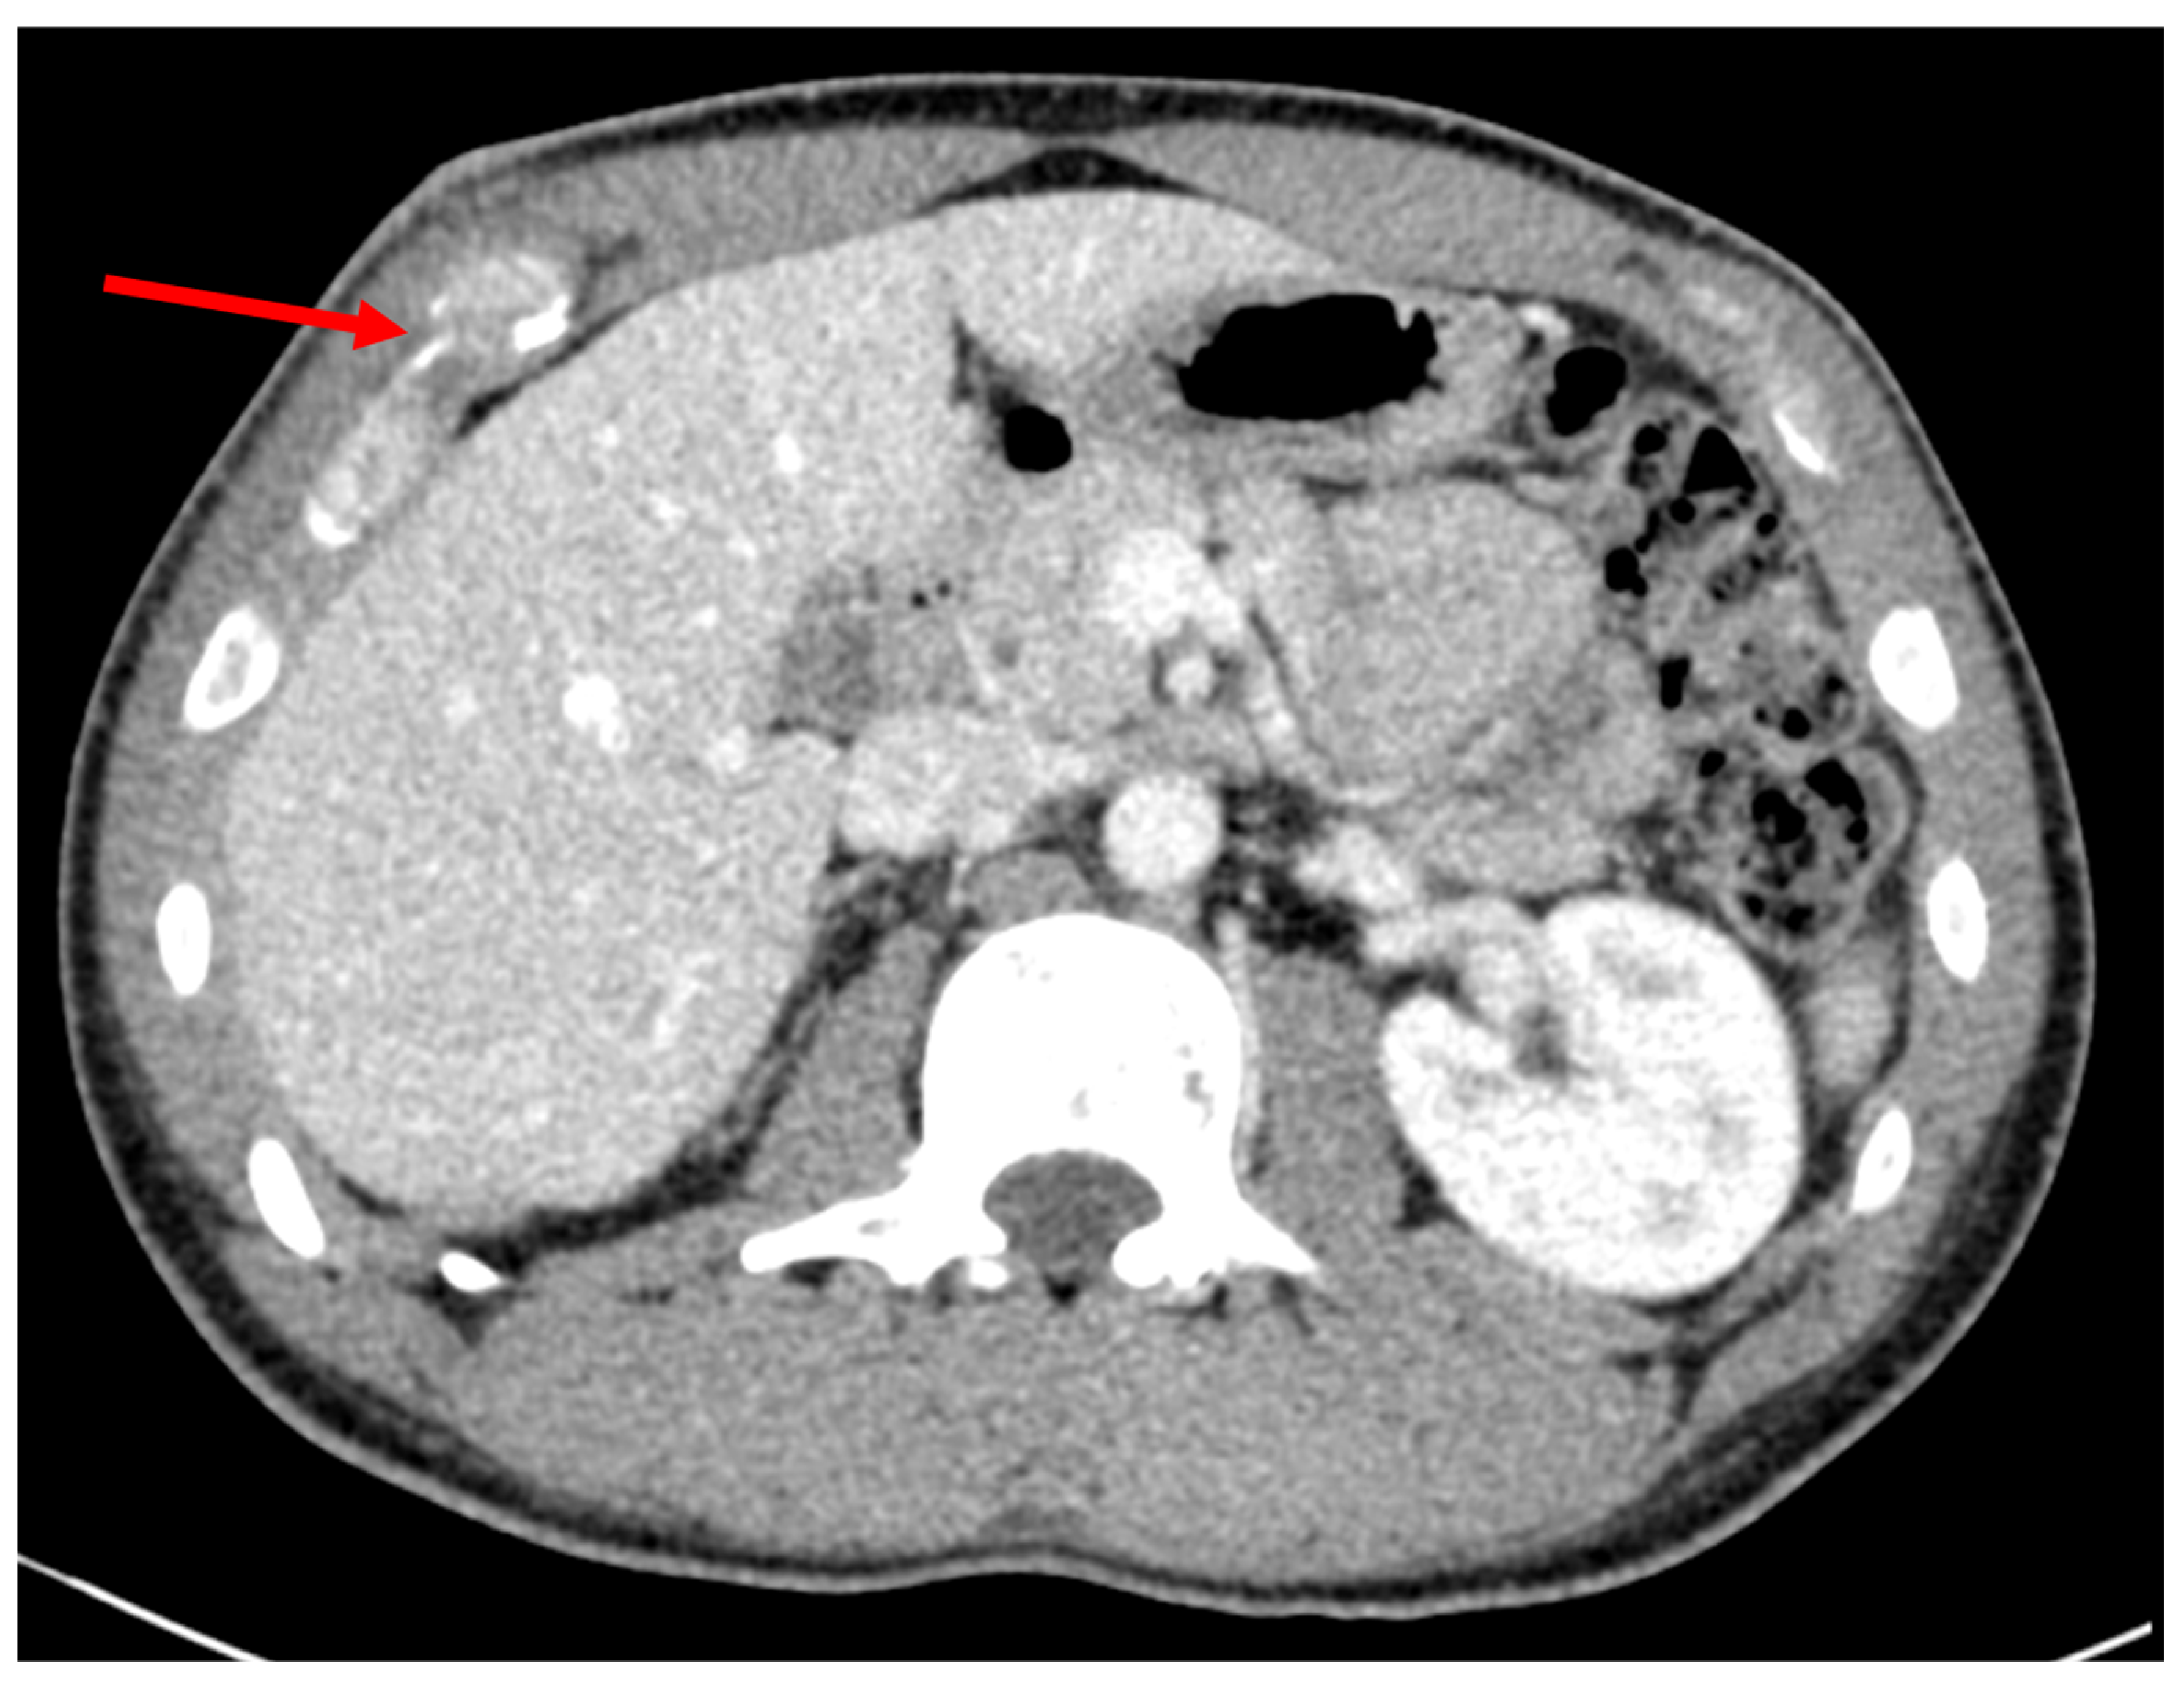

Figure 1.

Malunion fracture of the costal margin. Red arrow points to the location of injury.